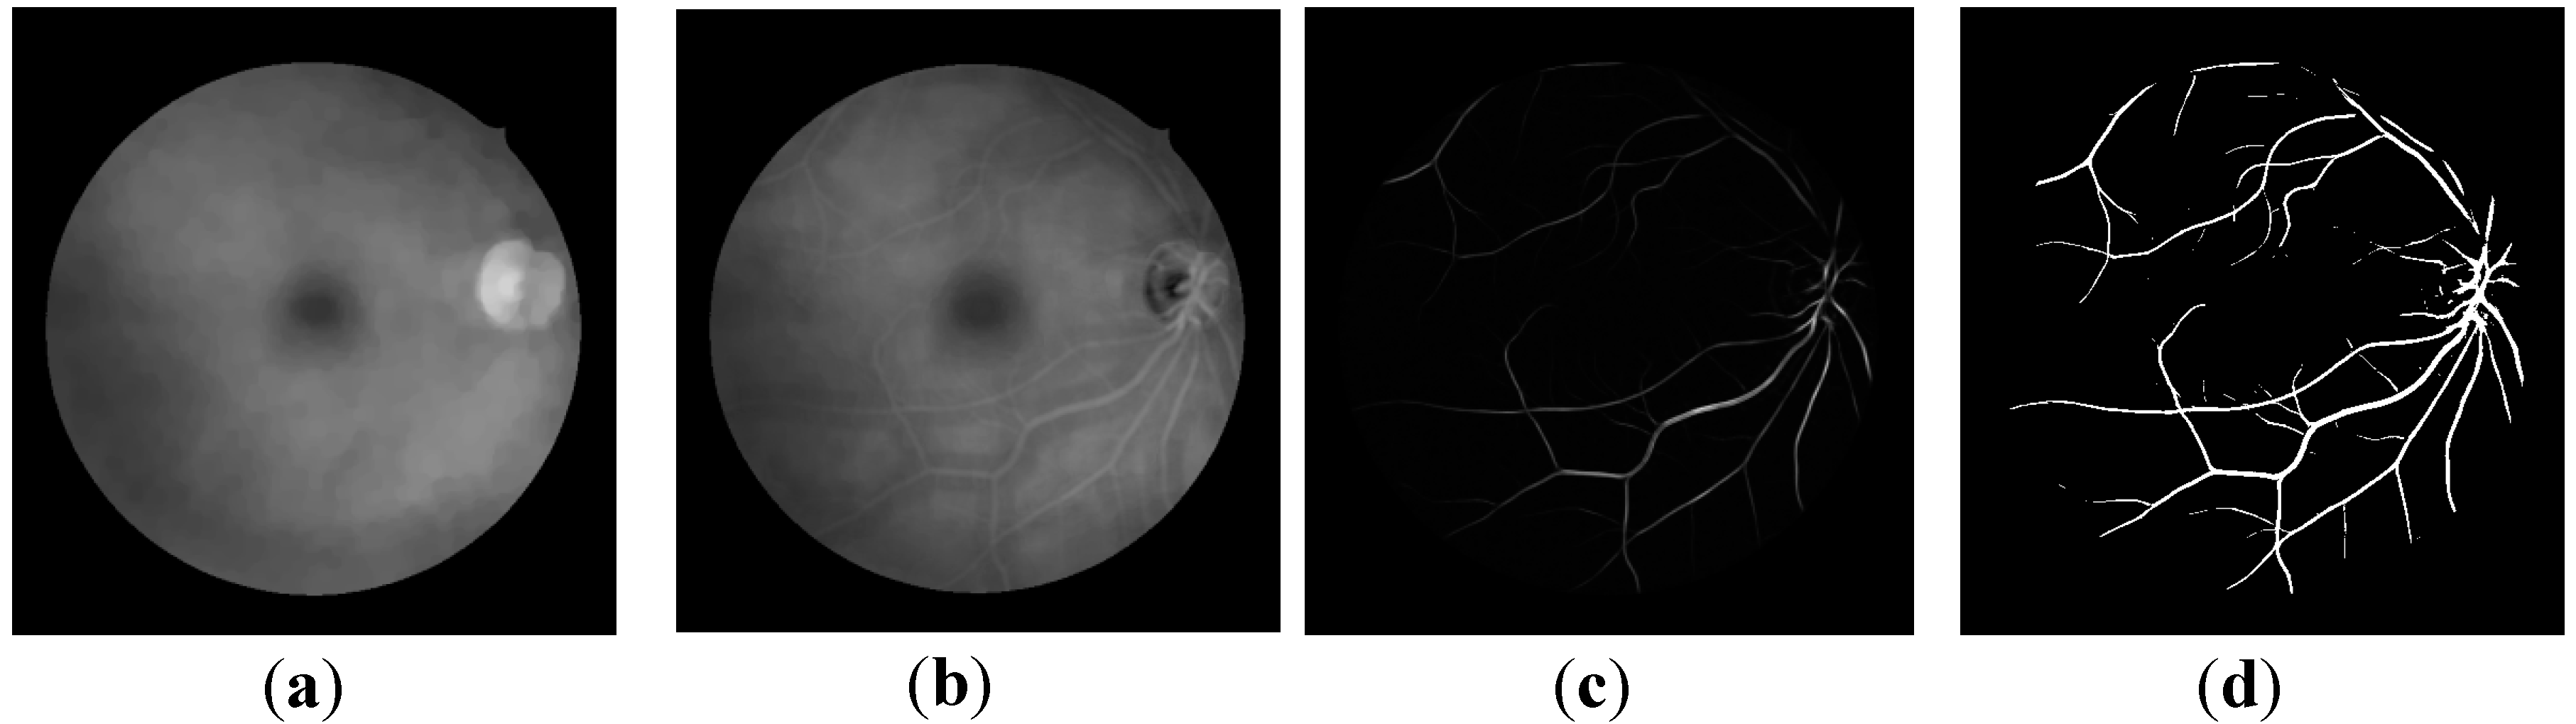

2.1. Illumination Correction

2.2. Optic Disc (OD) Localization

2.3. Retinal Vessel Segmentation